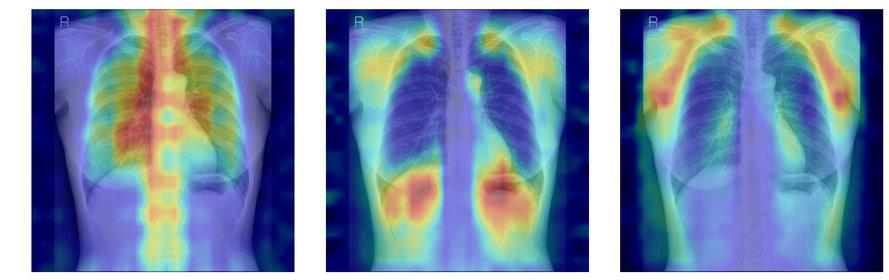

흉부X선에서 파운데이션 모델이 골다공증 판독을 위해 주목한 영역을 시각화한 이미지.

연구팀은 여기에 더해 AI가 실제로 어떤 뼈를 근거로 삼아 판단하는지까지 확인할 수 있도록 ‘설명 가능성’ 평가 체계를 설계했다. 뼈를 모두 가린 상태에서 특정 뼈 부위를 추가해 성능이 얼마나 향상하는지 확인하는 ‘차단 분석 방식(Δbone)’과 Grad-CAM으로 나타난 AI의 주목 영역이 실제 뼈 위치와 얼마나 일치하는지를 계산하는 ‘유의성 지도 방식(IoUbone)’을 통해, AI가 임상적으로 중요한 뼈 구조를 근거로 판단하는지를 정량적으로 검증했다.